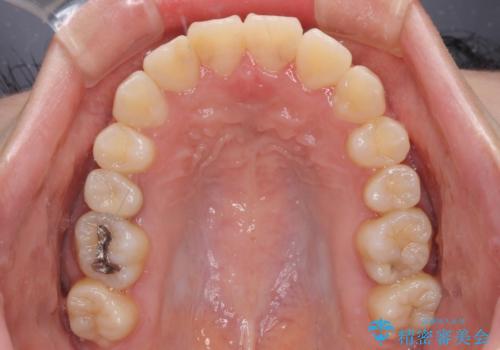

- 上下のデコボコと前歯のクロスバイトを改善したいとのことで来院された患者様です。

極力短期間で治療したいとのことで、ワイヤー装置による矯正治療を行うこととしました。

マウスピースによる矯正治療も提案しましたが、ご自身でのマウスピースの管理の面倒くささと、なるべく早く治療を終えたいとのことで、ワイヤー矯正を選択されました。